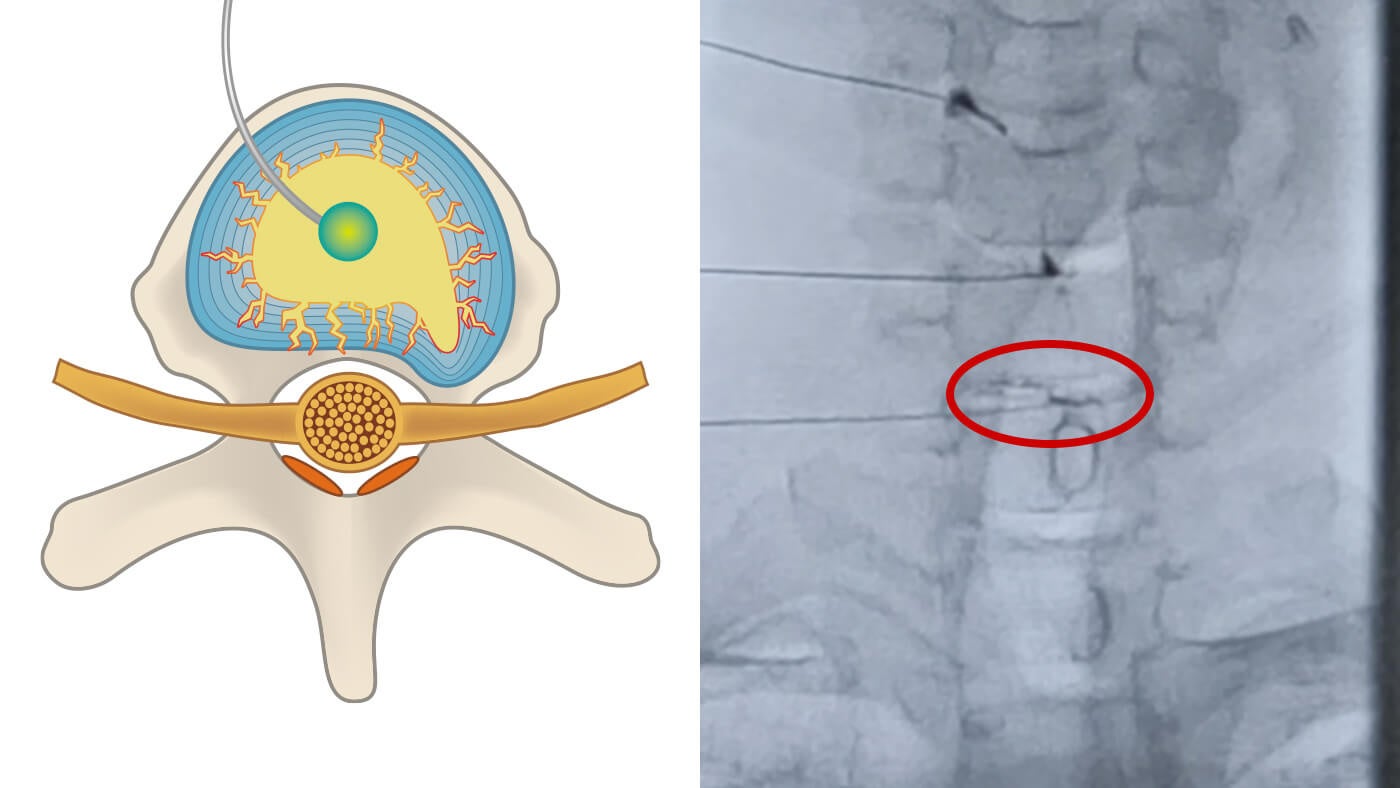

近年の研究では、神経の圧迫だけでなく、損傷した椎間板から内容物が「漏れ出す」ことによる炎症が症状の原因として注目されています。しかし、一般的なMRI検査ではこの「漏れ」まで特定することが難しく、原因が究明されないまま症状が長引くケースも報告されています。

損傷した椎間板に直接治療薬を注入することで、椎間板の亀裂を密封し、炎症に関与する症状の改善を目的としています。

● 椎間板の「漏れ」を椎間板造影検査(アニュログラム)で特定し、直接アプローチ